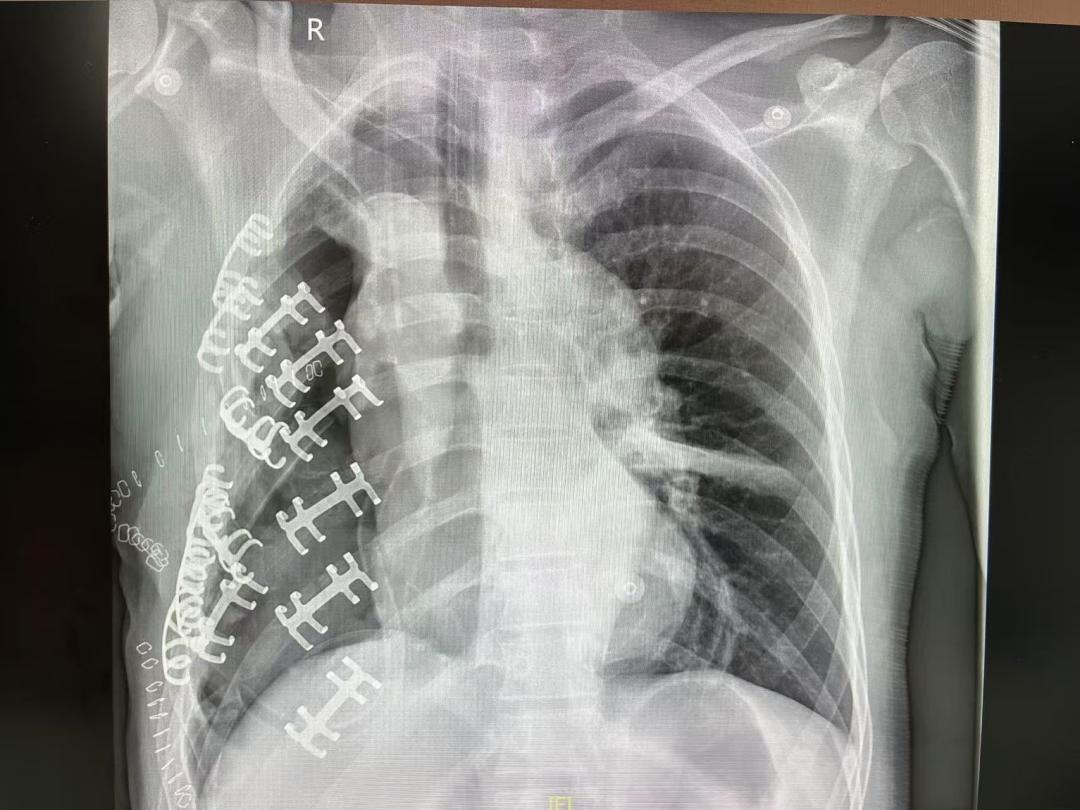

经过7小时鏖战,肿瘤终被完整切除,陈先生成功过了第一关。但第二关的难度也不容小觑,因为涉及8根肋骨的精细复位。吴源周说:“我们保留了患者自体肋骨,并采用记忆合金固定器来准确复位、固定肋骨骨折的断端,避免植入过多替代肋骨的钛板发生异物反应,最大限度恢复胸廓外形的同时有利于伤口的愈合。”

术后“原装”肋骨复位。